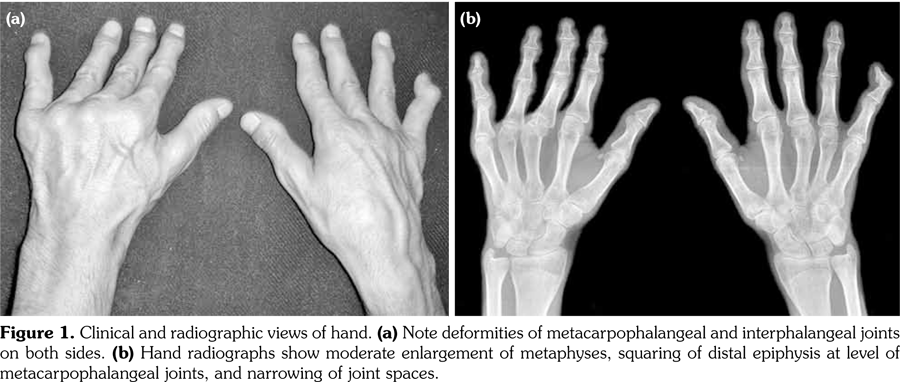

Physical examination revealed decreased range of motion in shoulders, wrists, metacarpophalangeal, proximal IP, distal IP, and ankle joints. In particular, the IP, metacarpophalangeal and metatarsophalangeal joints had bony enlargements, mild tenderness and flexion contractures; however, no signs of inflammation like redness, effusion, or other signs of synovitis (Figure1). The patient also had mild spinal scoliosis, significant thoracolumbar kyphosis, and pectus excavatum deformity. Furthermore, he had saddle nose deformity, bilateral floppy pinna and audiovestibular dysfunction (sensorineural hearing loss and tinnitus) (Figure 2). The rest of the systemic examination was unremarkable.

Radiographs of the hands showed enlargement of metaphyses, flattening of epiphyses, and narrowing of joint spaces with no erosions. Lateral radiograph of the foot revealed bilateral large ossified trigonum attached to the talus (mega os trigonum) (Figure 3). Radiographs of the spine showed increased kyphosis, generalized platyspondyly particularly at the thoracolumbar junction, and irregularity of the vertebral end- plates (Figure 4). Magnetic resonance imaging of thoracolumbar spine demonstrated irregularity in vertebral end-plates, multiple disk herniations, and platyspondyly (Figure 5). Dynamic contrast- enhanced magnetic resonance imaging of the wrist did not reveal any signs of synovial inflammation.